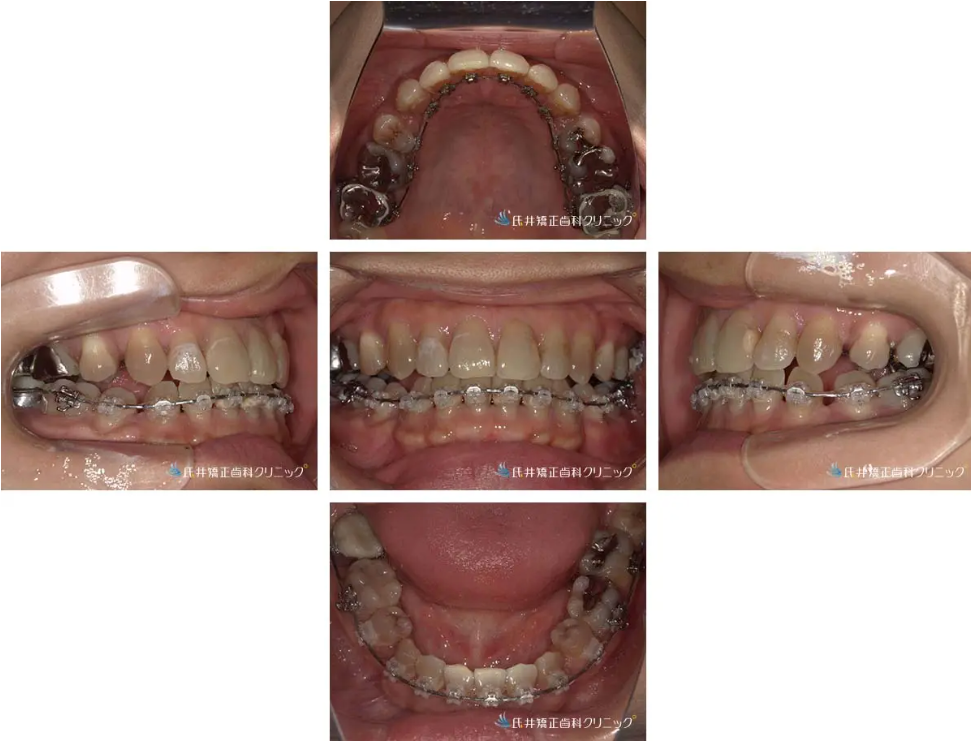

治療経過③:12か月後の状態(上の歯が整い、下の調整へ)

治療開始から12か月。

ガタガタだった前歯がきれいに並び、正面から見ても歯列のアーチが自然に整いました。

上の裏側装置も違和感なく、見えない位置からしっかりコントロールできています。

咬み合わせも安定してきており、治療は仕上げの微調整段階へ進んでいます。

必要に応じてエラスティック(顎間ゴム)を併用し、最終的な咬合の安定化を図ります。

治療完了:2年後の状態

治療開始から2年で、ガタガタだった前歯がきれいに整いました。

上の歯は裏側から矯正していたため、装置が見えないまま治療を進めることができました。

咬み合わせも安定し、横顔のラインもすっきりと変化。

見た目だけでなく、機能的にもバランスの取れた仕上がりとなりました。